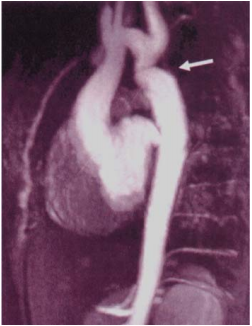

76 5 歲男童有心雜音,MRA(Magnetic resonance angiography)如圖示,則最正確的診斷應為:

(A)主動脈弓窄縮(coarctation of aorta) (B)主動脈瓣狹窄(aortic stenosis) (C)主動脈瓣閉鎖不全(aortic regurgitation) (D)主動脈剝離(aortic dissection)